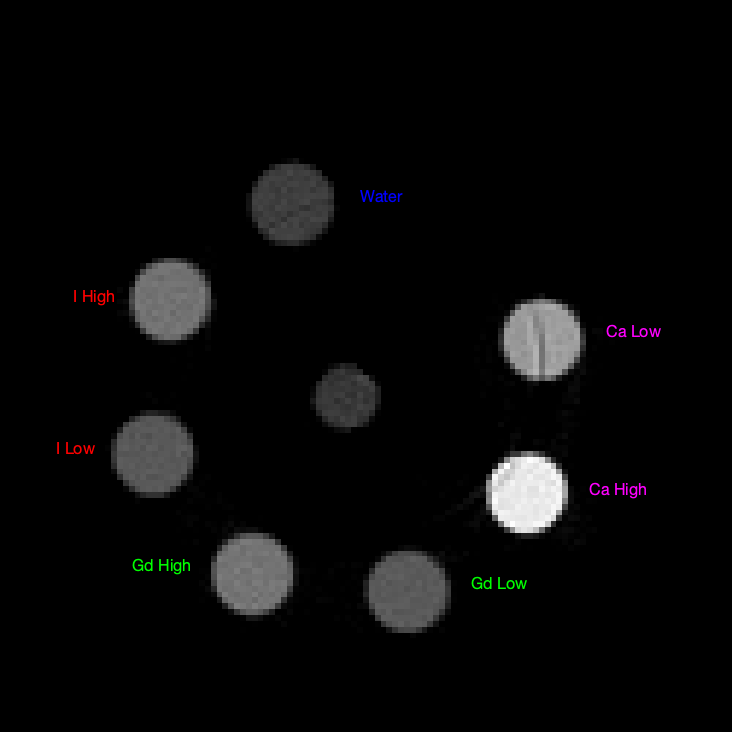

Refer to caption

Figure 1: Material Concentration and spatial location

Phantom solutions were created with varying concentrations of iodine, gadolinium, and calcium in water in 7 tubes. Please refer to Table I for concentration and spatial information of different solutions. Note that iodine, gadolinium, and calcium are not mixed with each other and are kept spatially orthogonal in this setup. We intend to mix contrasts in our future work. K𝐾K-edges of iodine and gadolinium are around 333333 KeV and 535353 KeV respectively. The bins are chosen to take advantage of the difference in the photon absorption properties of different basis materials. Some defective detector pixels did not register any signal, or were unreliable, and data correction was therefore performed to eliminate outliers and make sinograms consistent. The first set of phantom solutions was used to calibrate the mixing matrix (please refer to the 2ndsuperscript2𝑛𝑑2^{nd} column of Table I). Then that mixing matrix was used in the forward model of reconstruction for a 2ndsuperscript2𝑛𝑑2^{nd} set of phantom data (please refer to the 3rdsuperscript3𝑟𝑑3^{rd} column of Table I).